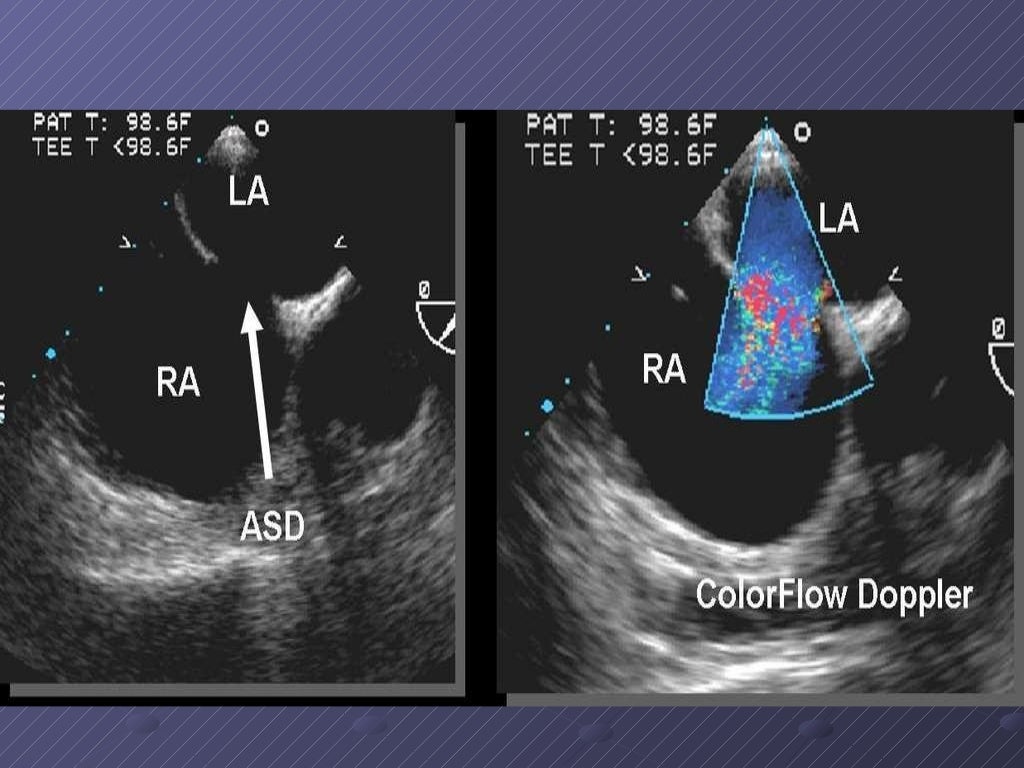

La comunicación interauricular (CIA) es una cardiopatía de origen congénito acianógena (sin cianosis), consistente en una deficiencia del septum o tabique que separa las cavidades del corazón denominadas aurículas y que resulta en una libre comunicación entre el lado derecho e izquierdo de las aurículas. Puede estar situada en cualquier parte del mismo, siendo su localización más frecuente en la región de la fosa oval y así se denomina tipo ostium secundum.

La presencia de esta comunicación origina un circuito anormal de sangre desde la aurícula izquierda hacia la derecha generando una sobrecarga en esta última, que con el tiempo y dependiendo del tamaño de la comunicación, repercute sobre el pulmón y el corazón, hecho que sucede en la adultez generalmente. Las CIA ocurren cuando el proceso de división no se produce por completo y queda una abertura en el tabique auricular.[1][2]

Diagnóstico